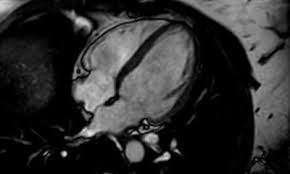

Während der untersuchung können sie wand, muskulatur, klappen und pumpleistung beurteilen. Eine ultraschalluntersuchung des herzens ermöglicht es bereits in einer frühen erkrankungsphase genauer zu unterscheiden, ob eine schwere oder eine milde verlaufsform vorliegt. Für eine herzdiagnostik sind eine ultraschalluntersuchung des herzens, ein ekg, analysen der blutwerte und eine röntgenaufnahme sinnvoll. Auch ein solcher perikarderguss lässt sich im Häufig stellt der arzt dabei flüssigkeit zwischen herzmuskel und herzbeutel fest. Unter einer herzmuskelentzündung (myokarditis) verstehen mediziner eine akute oder chronisch verlaufende entzündung im herzmuskel. Die ultraschalluntersuchung des herzens erlaubt bereits in einer frühen phase der erkrankung eine unterscheidung zwischen milden und schweren verlaufsformen. Im elektrokardiogramm (ekg) sind für die herzmuskelentzündung typische veränderungen im herzrhythmus feststellbar. Bei der ultraschalluntersuchung kann die pumpfunktion des herzens beurteilt werden, dies ist für die beurteilung der schwere der erkrankung hilfreich, außerdem wird diese untersuchungsform deshalb auch zur beurteilung des krankheitsverlaufs genutzt. Ein großteil der herzmuskelentzündungen geht mit nur leichten symptomen einher und heilt spontan wieder ab. In leichten fällen reicht körperliche schonung als therapie. Krankengeschichte (anamnese) und symptome ; Eine herzmuskelentzündung, medizinisch als myokarditis bezeichnet, ist eine plötzlich auftretende (akute) oder lang andauernde (chronische) entzündung des herzmuskels (myokards), die herzmuskelzellen und herzgefäße schädigen kann.

Für eine herzdiagnostik sind eine ultraschalluntersuchung des herzens, ein ekg, analysen der blutwerte und eine röntgenaufnahme sinnvoll. Die herzhöhlen (herzkammern und vorhöfe) sind fast immer unnatürlich vergrößert. Ist der herzbeutel und der herzmuskel entzündet, ist dies eine perimyokarditis. Welche herzuntersuchungen gibt es noch? Unter einer myokarditis, also einer herzmuskelentzündung, ist ein entweder akut oder chronisch verlaufender entzündungsprozess.

Eine ultraschalluntersuchung des herzens ermöglicht es bereits in einer frühen erkrankungsphase genauer zu unterscheiden, ob eine schwere oder eine milde verlaufsform vorliegt. Dazu zählen die impfungen gegen grippe und diphtherie. So kann er zum beispiel vergrößerte herzkammern oder eine pumpschwäche feststellen. Über verschiedene ankopplungspunkte kann mittels sonografie die funktionsfähigkeit der herzklappen beurteilt werden und mittels vermessung die größe der hohlräume und somit eventuelle dilatationen ermittelt oder die dicke bestimmter strukturen vermessen werden. Eine herzbeutelentzündung wird als perikarditis bezeichnet. Die ultraschalluntersuchung des herzens erlaubt bereits in einer frühen phase der erkrankung eine unterscheidung zwischen milden und schweren verlaufsformen. Ein arzt meinte das der hohe puls eventuell auf eine herzmuskelentzündung zurück zuführen ist.der ultraschall war jedoch in ordnung. Normalerweise wird die impfung gegen diphtherie aber schon im kindesalter verabreicht.

Erschwerend kommt hinzu, dass viele betroffene kaum. Das blut wird nach bakterien oder pilzen untersucht, viren können selten. Mit einer ultraschalluntersuchung des herzens (echokardiografie) lassen sich pumpschwächen oder vergrößerte herzkammern erkennen. Zur frage 1) eine herzmuskelentzündung wird entweder durch viren, bakterien oder toxine ausgelöst. Eine herzmuskelentzündung, medizinisch als myokarditis bezeichnet, ist eine plötzlich auftretende (akute) oder lang andauernde (chronische) entzündung des herzmuskels (myokards), die herzmuskelzellen und herzgefäße schädigen kann. Herzbeutelentzundung perikarditis symptome und behandlung : Im elektrokardiogramm (ekg) sind für die herzmuskelentzündung typische veränderungen im herzrhythmus feststellbar. Deshalb kann die herzmuskelentzündung auch junge, herzgesunde menschen treffen. Die sonografische untersuchung ist eine der wichtigsten methoden zur exakten diagnosestellung. Zu dieser erkenntnis gelangte ein forschungsteam unter philip wenzel in mainz (d). Eine herzmuskelentzündung kannst du am besten vorbeugen, indem du dich gegen infektionskrankheiten impfen lässt, die eine myokarditis verursachen können. Häufig stellt der arzt dabei flüssigkeit zwischen herzmuskel und herzbeutel fest. In leichten fällen reicht körperliche schonung als therapie.